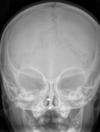

Head And Neck Flashcards

(292 cards)